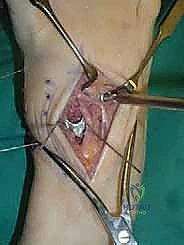

2. الشق الجراحي والوصول للمفاصل

يتم عمل شق جراحي واحد أو شقين (أحدهما في الجزء العلوي الداخلي والآخر في الجزء الخارجي) للوصول إلى مفاصل منتصف القدم دون الإضرار بالأوتار الحيوية والأعصاب والأوعية الدموية. يتم استخدام تقنيات الجراحة الدقيقة (Microsurgery) للحفاظ على الأنسجة المحيطة السليمة.

3. إزالة الغضاريف التالفة (Joint Preparation)

هذه هي الخطوة الأهم. يقوم الجراح بكحت وإزالة جميع الغضاريف المريضة والتالفة من بين العظام المراد دمجها. يجب الوصول إلى العظم الإسفنجي الصحي (Cancellous bone) الذي ينزف دماً، لأن هذا الدم يحتوي على الخلايا الجذعية وعوامل النمو الضرورية لعملية الالتحام (Fusion).